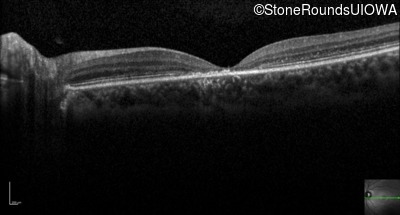

Optical Coherence Tomography - Right - 20/160 +1

Exemplar / OCT Stack

Optical Coherence Tomography - Left - 20/125 -1